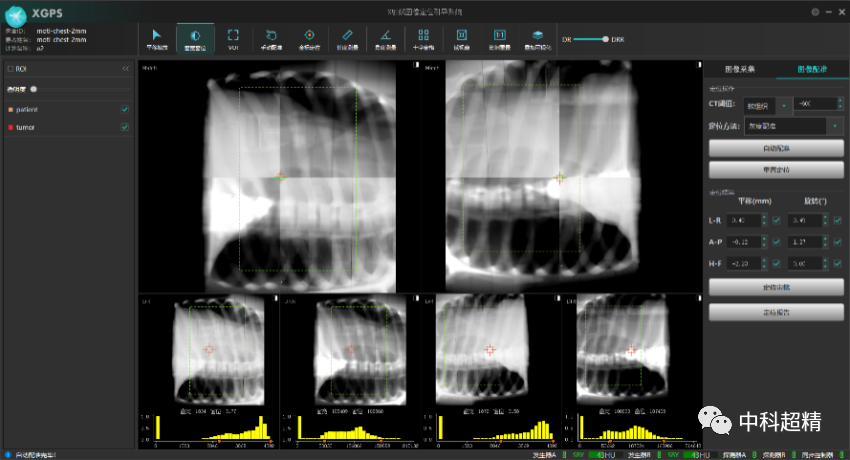

“麒麟刀·木” X射線圖像引導(dǎo)系統(tǒng)

(KylinRay-XGPS)

KylinRay-XGPS是面向腫瘤放射治療的圖像引導(dǎo)系統(tǒng),主要基于透視成像對(duì)腫瘤患者放射治療過程實(shí)施精確定位,是中科超精在精準(zhǔn)照射領(lǐng)域布局的另一重磅產(chǎn)品。該系統(tǒng)采用KV級(jí)透視成像和圖像智能配準(zhǔn)技術(shù),基于放射治療計(jì)劃以及三維CT圖像生成DRR圖像與采集投影圖進(jìn)行2D-3D圖像配準(zhǔn),精確探測(cè)出 6個(gè)自由度的擺位誤差,真正實(shí)現(xiàn)了對(duì)患者在每個(gè)分次的高質(zhì)量圖像引導(dǎo)。此產(chǎn)品可以獨(dú)立安裝,無需與直線加速器建立電氣連接,可適應(yīng)各種主流加速器型號(hào)以及不同結(jié)構(gòu)的機(jī)房,并幫助廣泛的用戶以最低的成本實(shí)現(xiàn)圖像引導(dǎo)的放射治療。